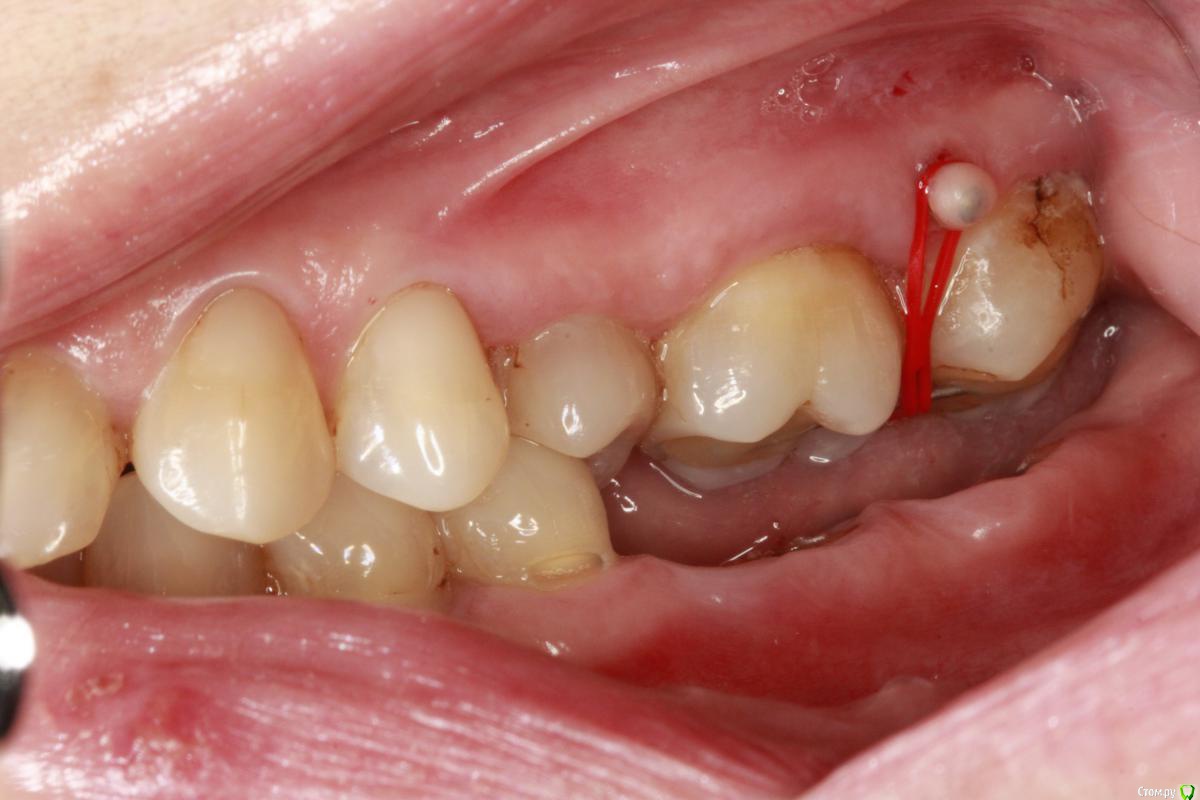

an_ver Опубликовано 9 июня, 2017 Поделиться Опубликовано 9 июня, 2017 (изменено) На корейских винтах. Сперва поднял,потом удалил низ,корни,вр.коронки,постоянные.46-47 касались ниж.десны.Активация-1 раз в неделю Изменено 9 июня, 2017 пользователем an_ver 1 Ссылка на комментарий